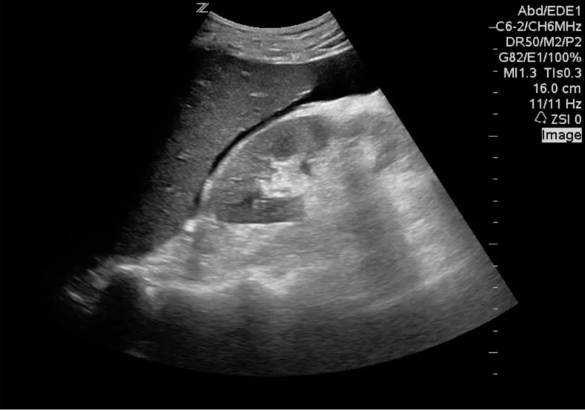

As we wait, a lovely US fellow comes around looking for people to scan…

He finally goes for imaging:

1. High-grade splenic injury/devascularization (AAST grade IV-V) with large volume hemoperitoneum. No evidence of active extravasation or pseudoaneurysm.

2. Hyperattenuating adrenal glands and mild flattening of the IVC, which can be seen in the setting of CT hypoperfusion complex.

3. No pneumoperitoneum or acute osseous abnormality.